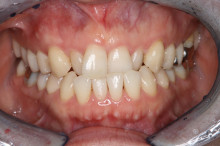

矯正終了

2年ほどかかりましたが、非常にきれいに歯が並びました。

一般の方は気づかないかもしれませんが、

下の前歯は3本しかありません。